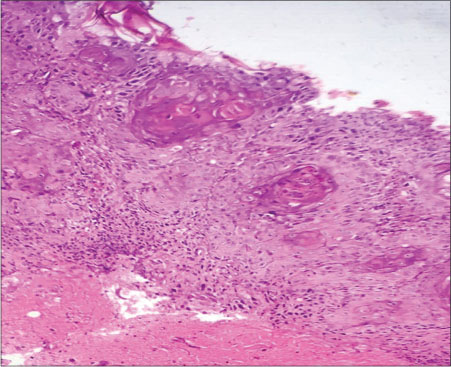

His hemoglobin was 13.5 g/dl with a total leukocyte count of 17,000 cells/mm3 and erythrocyte sedimentation rate was 87 mm in the 1st h. Liver and kidney function tests were within normal limits. Repeated swabs from the ulcerated site for culture revealed a mixture of organisms. The histopathology of the wedge biopsy from the edge of the ulcerated growth showed dysplastic squamous epithelium and tumor cells arranged in nests and cords, oval to polygonal in shape with eosinophilic cytoplasm and keratin pearls, favoring the diagnosis of a well-differentiated squamous cell carcinoma (SCC) [Figure 3]. A punch biopsy from the adjacent erythematous scaly plaque confirmed the diagnosis of psoriasis [Figure 4]. Fine-needle aspiration cytology from the inguinal lymph nodes was free from tumor cells.

| Figure. 3 Hematoxylin and eosin stain under ×10 magnification shows dysplastic squamous epithelium and tumor cells arranged in nests and cords with oval to polygonal shape and eosinophilic cytoplasm along with keratin pearls, suggestive of a well-differentiated squamous cell carcinoma

| Figure. 4 Hematoxylin and eosin stain under ×10 magnification shows epidermal parakeratosis, hypogranulosis, elongation of rete ridges, and dilatation of dermal papillae, suggestive of psoriasis